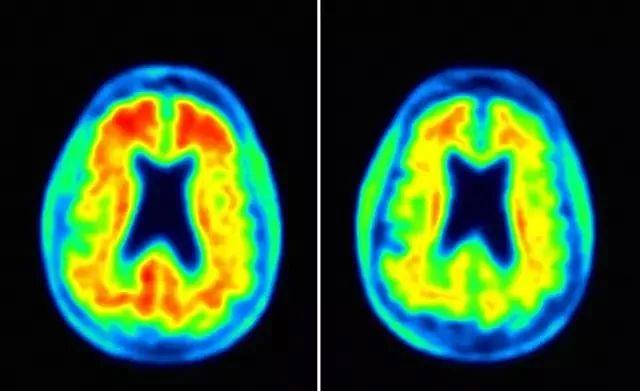

Aducanumab治疗(右)可减少淀粉样蛋白斑块 图片来源:Fortune

然而,在宣布终止临床试验后,百健对包含全部3285名患者的数据集进行了分析,发现在EMERGE的临床试验中,接受高剂量(10 mg/kg)aducanumab治疗的AD患者,认知能力评分与对照组相比降低了23%,获得了显著统计学意义上的改善。而在ENGAGE的临床试验中,持续接受高剂量aducanumab治疗的部分患者的认知能力也得到了提高。这些患者在认知和功能测试(如记忆、定向和语言)方面有显著改善,也可以更好地处理个人财务、做家务,甚至独自出门旅行。